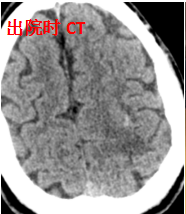

面对这一突发状况,周元主任指导调整治疗方案,护理团队日夜守护,精准调控血压,患者和家人全力配合治疗!患者的病情逐步好转,最终康复出院,重获行走能力。